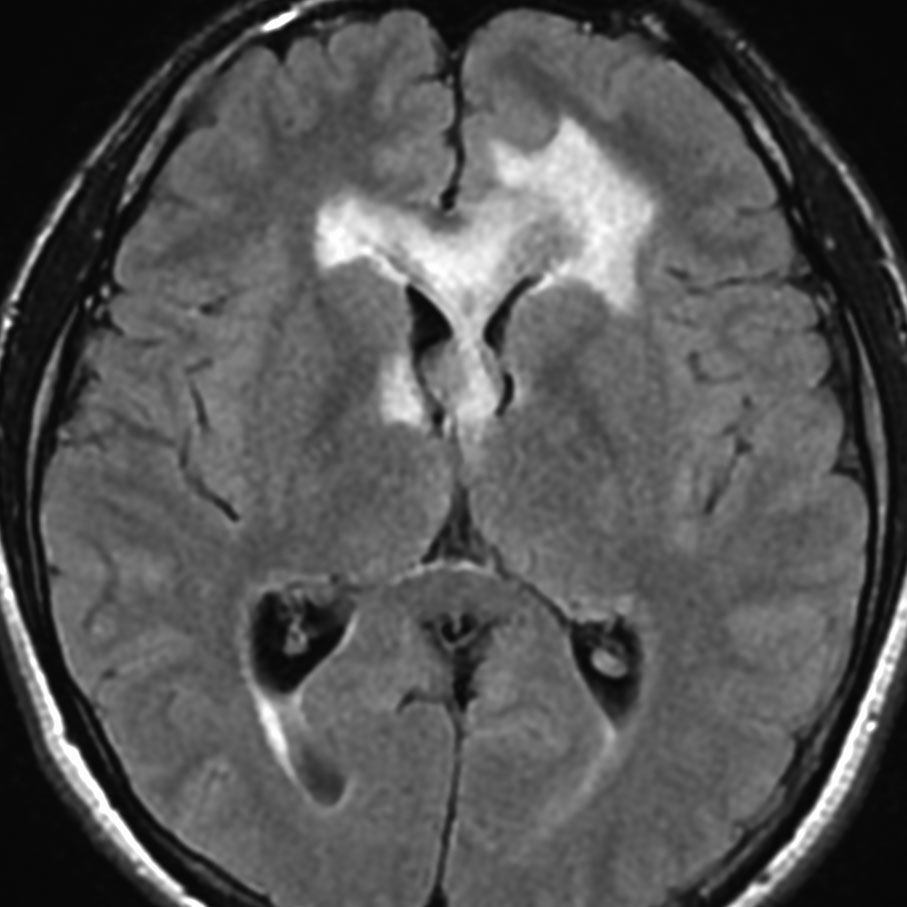

左はICE化学療法 (IFO/CDDP/VP-16)前,右は1コース終了後です。腫瘍は顕著に縮小してgerminomaとして普通の化学療法反応性を示します。また,松果体と下垂体には腫瘍はありません。

ICEを3コース行なって腫瘍は完全消失して,前頭葉浮腫も消えました。その後に,全脳照射 25.2Gy/14分割を加えました。無症状で復職することができました。